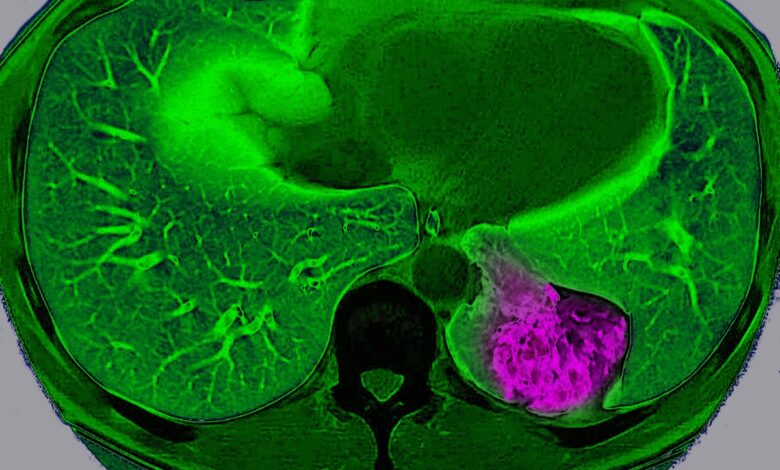

Lung cancer on the left pulmonary lobe, seen on a radial section MRI scan of the chest.

BSIP/Universal Images Group via Getty Images